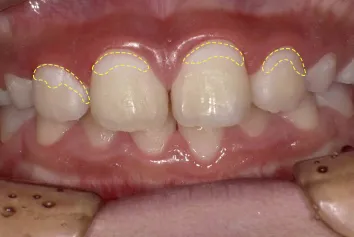

写真2 2週間後

このような状態をエナメル質初期う蝕(Ce)と呼び、この段階では、歯を削らずに治す「非修復治療」が適応となります。写真2の歯は2週間で溶け出したエナメル質の結晶が、また歯に戻って来ました(再石灰化)。